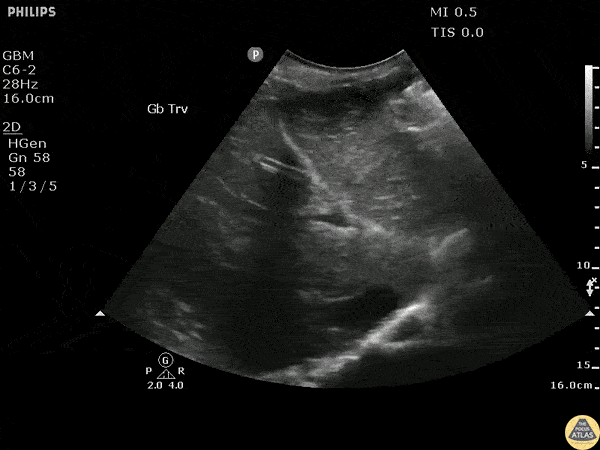

Transverse scan of the liver shows diffuse dilation of intrahepatic biliary ducts. Image courtesy of Robert Jones DO, FACEP @RJonesSonoEM Director, Emergency Ultrasound; MetroHealth Medical Center; Professor, Case Western Reserve Medical School, Cleveland, OH View his original post here